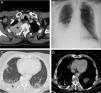

A)Imagen axial de TC de tórax (ventana de mediastino) realizada en 2012 en la que se identifica una masa sólida en hemitórax superior derecho (asterisco) que infiltra la pared torácica y se introduce en el canal raquídeo a través del agujero de conjunción T2-T3 derecho (flecha). B)Radiografía posteroanterior de tórax realizada en noviembre de 2017 en la que se detecta, por primera vez en el paciente, un derrame pleural derecho. C)Imagen axial torácica de un estudio de PET/TC realizado en noviembre 2017 en el que se identifican opacidades bilaterales de aspecto neumónico (flechas) y un derrame pleural derecho (asterisco). D)Imagen axial torácica de otro estudio de PET/TC realizado en marzo de 2018 en las que observa una desaparición de las opacidades neumónicas y la presencia de mínimo derrame pleural.

Se trata de un varón de 67años con antecedentes de un MM quiescente IgA Kappa diagnosticado en 1998 que acudió a urgencias de nuestro hospital en noviembre de 2017 por presentar fiebre, mal estado general, astenia y tos. El paciente presentó varios plasmocitomas con afectación de la pared torácica derecha (fig. 1A) y del canal raquídeo en 2012 y 2014, pero sin DP, que fueron tratados con diferentes opciones terapéuticas (quimioterapia, trasplante autólogo de progenitores hematopoyéticos, radioterapia local), lográndose una respuesta completa de dichas lesiones. En 2015 presentó una nueva recaída extramedular en forma de una masa paravertebral en hemitórax derecho que fue tratada con quimioterapia. Dados la clínica del paciente y el hallazgo radiográfico (no presente en estudios previos) en urgencias de un DP derecho (fig. 1B), se decidió el ingreso del paciente y la realización de una tomografía por emisión de positrones/tomografía computarizada (PET/TC). La PET/TC demostró opacidades pulmonares bilaterales hipermetabólicas de aspecto neumónico y confirmó un DP derecho de moderada cuantía (fig. 1C). Se obtuvo líquido pleural de aspecto serohemático con las siguientes características: pH 7,43, glucosa 104mg/dl (glucosa sérica 91mg/dl), lactato 3,2mmol/l, ratio proteína líquido pleural/proteína sérica: 0,70, ratio LDH líquido pleural/LDH sérico: 2,37, LDH líquido pleural: 524, hematocrito <15%, linfocitos 28,7%, neutrófilos 0,0% (criterios de exudado linfocitico) y estudio microbiológico negativo, descartándose así una causa infecciosa del DP. En la citometría de flujo del líquido pleural se detectó un 60% de células plasmáticas tumorales de tamaño grande (células plasmablásticas) CD 138+ y CD 56−, que confirmó la naturaleza maligna (mielomatosa) del DP. Una biopsia de mucosa yugal descartó la presencia de depósitos amiloideos. El paciente en un principio fue tratado con antibióticos (piperacilina-tazobactam) y posteriormente se realizó drenaje pleural derecho seguido de pleurodesis química con talco, radioterapia local y quimioterapia (pomalidomida-dexametasona-ciclofosfamida), presentando una excelente evolución clínica y radiológica (fig. 1D).